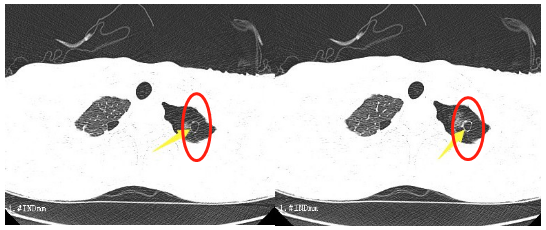

这段时间,16岁的小王突然出现了胸闷的症状,持续一周都不见好转。到我院胸心外科检查后,胸片提示左侧液气胸,积气为主,结合患者术前CT检查情况,考虑为肺大泡破裂引起的气胸。